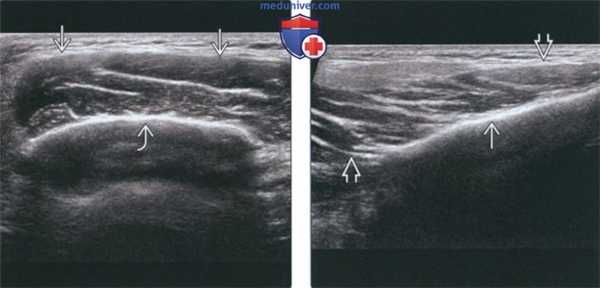

2. УЗИ при доброкачественной гипертрофии жевательной мышцы:

• Увеличение жевательной мышцы, обычная эхогенность, ровные контуры

• Отсутствие очагов, неоднородности, кальцинатов, кист в мышце

• Подлежащая кортикальная пластинка нижней челюсти может быть неровной, что позволяет предположить гиперостоз

• Цветовая допплерография: патологические сосуды в мышце отсутствуют

о Из-за поверхностной локализации жевательной мышцы УЗИ идеально подходит для диагностики и мониторинга лечения

о Всегда сравнивайте мышцы в определенных точках: угол нижней челюсти, уровень мочки уха, а также в середине расстояния между ними

о УЗИ идеально подходит для контроля положения иглы при инъекции ботулотоксина А для коррекции ДГЖМ, а также динамического контроля

(Слева) УЗИ, поперечная проекция: определяется диффузное увеличение жевательной мышцы. В норме на УЗИ поперечник жевательной мышцы (Справа) УЗИ, поперечная проекция: визуализируется неизмененная жевательная мышца с противоположной стороны. Подлежащая кортикальная пластинка нижней челюсти ровная.